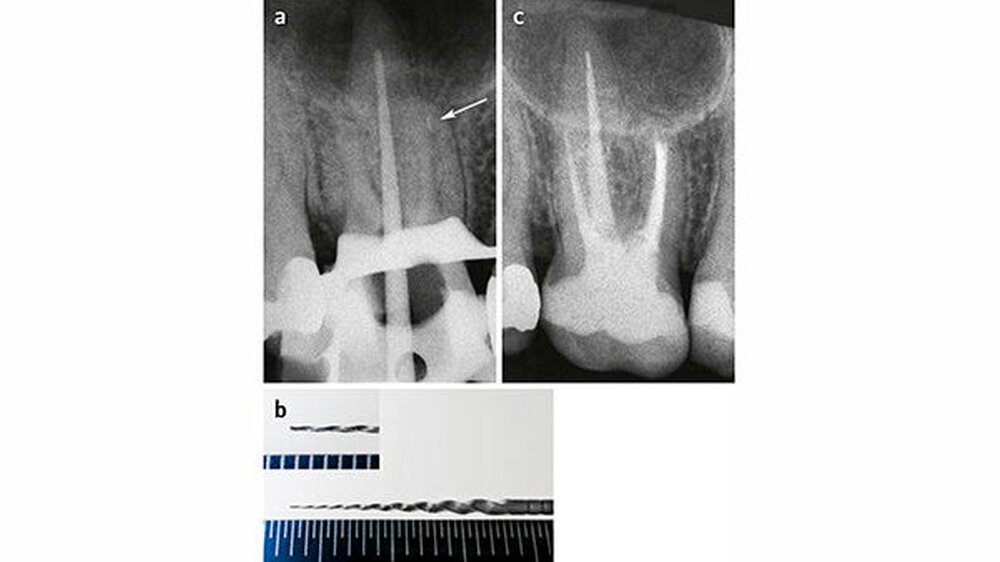

In einer Nachfolgeuntersuchung zu unserer eigenen Studie stellte Helbling (2014) fest, dass es keinen Unterschied bezüglich des klinischen Erfolgs nach ≥ 3 Jahren gab, wenn das frakturierte Instrument nicht vollständig entfernt werden konnte und/oder es anlässlich des Entfernungsversuchs zur Perforation gekommen war, verglichen mit Zähnen mit erfolgreicher Instrumentenentfernung (Abb. 4 und 5). Das Untersuchungsgut lässt außerdem die Vermutung zu, dass die Stärke der Kanalkrümmung die Erfolgswahrscheinlichkeit bezüglich Instrumentenentfernung beeinflusst. Wegen der kleinen Anzahl der Fälle sind diese Ergebnisse jedoch nicht abschließend.